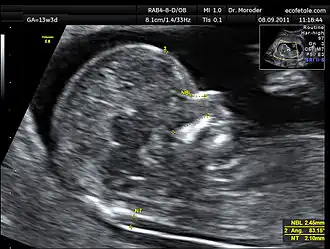

De nekplooimeting is een echografisch onderzoek van de foetus, tussen de 11e en 14e week van de zwangerschap, waarbij de dikte van de nekplooi wordt gemeten. De plooi die op de echo wordt gezien is niet een echte plooi in de huid maar een tijdelijke ophoping van vocht onder de huid die bij elke foetus kan worden aangetoond. Een verdikte nekplooi (meer dan 3 mm) op de echo kan duiden op een chromosoomafwijking, waarvan het syndroom van Down de meest voorkomende is. Ook kan sprake zijn van een hartafwijking. Bij de risicoinschatting op de ziekte van Down wordt de nekplooimeting samen met de uitslagen van een bloedtest (combinatietest) en de leeftijd van de moeder omgezet tot een individuele risicoinschatting. De diagnose syndroom van Down zal met verdere diagnostiek moeten worden vastgesteld.

In het algemeen zal bij vaststelling van een verdikte nekplooi een vlokkentest of vruchtwaterpunctie nodig zijn om specifieke aangeboren afwijking vast te stellen. De nekplooimeting geeft namelijk slechts een risico aan.